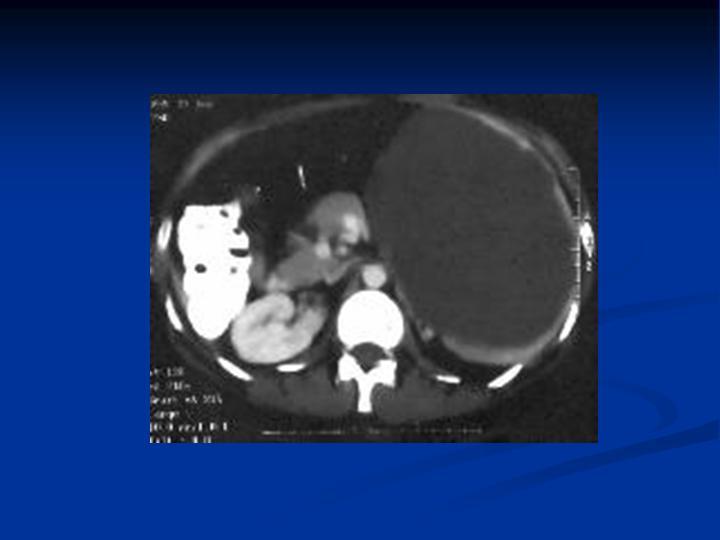

Trauma Esplénico